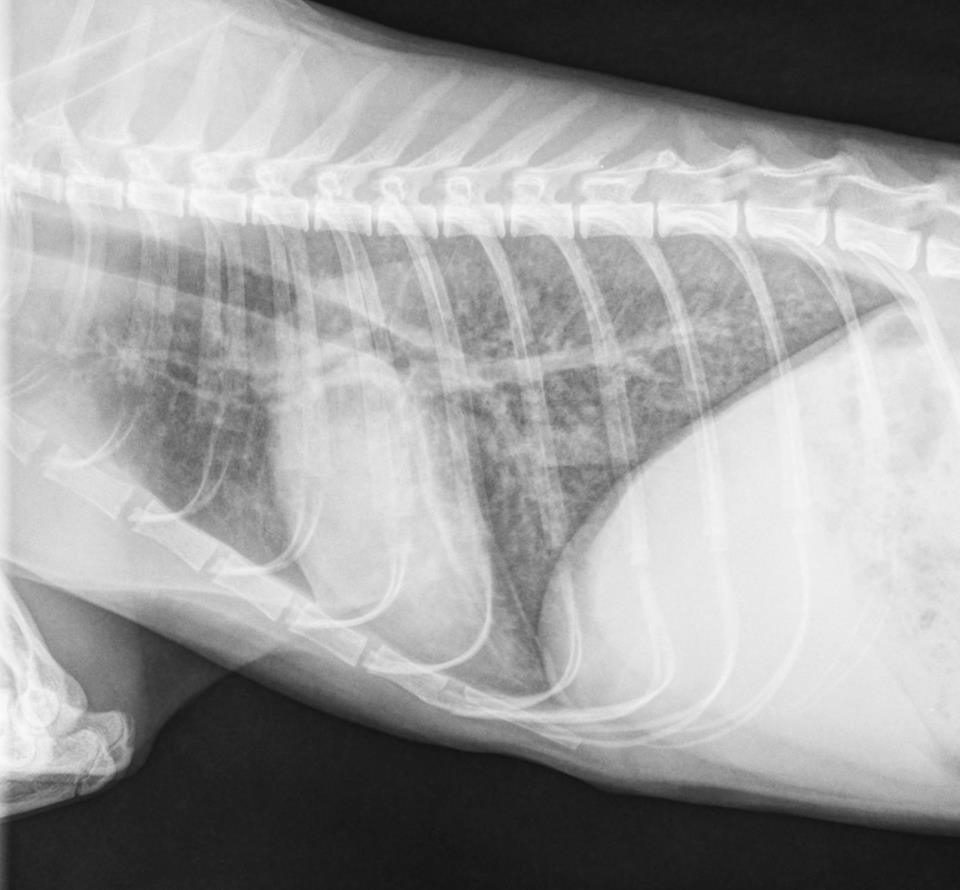

- Image interpretation is what we do all day long, and we are good at it!

- Significant findings are often overlooked because they are not recognized in the images. This is one of the primary reasons to use us!

- There is a high incidence of over-interpretation of common imaging findings (perceived loss of abdominal detail, splenomegaly, interstitial pattern, etc.). We can help tell you whether these findings are significant and need further evaluation.

- It is always a good idea to have at least two people (you and us) evaluate images in a team-based approach.

- Having all of your studies interpreted is taking the quality of medicine you practice to the next level.